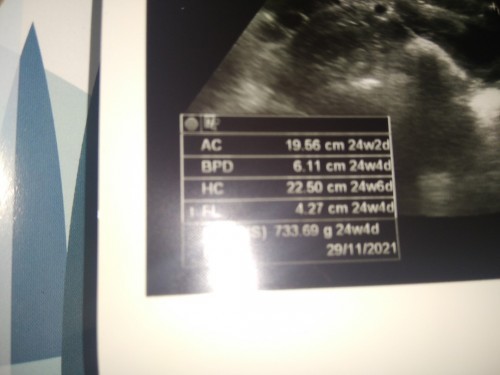

อายุครรภ์ตอนนี้เท่ากับ24w4dจามใบอัลตร้าซาวด์ด้านล่างรึเปล่าคะ